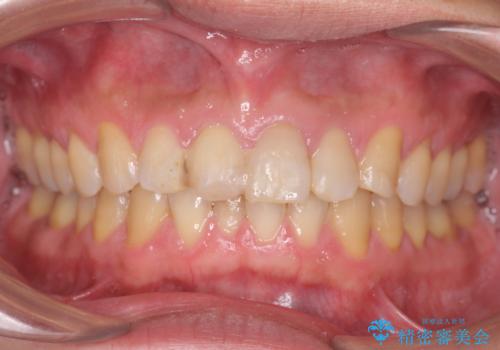

転んで前歯が欠けてぐらぐらに 歯の神経も死んでしまった

- 転倒して前歯を強打してかけてしまった、ぐらつくとのことで来院。

応急でみてもらった歯科医院で隣の歯と接着剤で留めてもらったとのこと。

歯の神経の状態を見たところ、前歯3本とも神経が死んでしまっていました。

また、左上犬歯の詰め物は途中で脱離し、セラミックでの修復をご希望されたため、一緒に治療しました。

根の治療を行い、ぐらつきに関しては様子を見て連結をするとのお話をさせていただきました。

結果ナイトガードの使用によりぐらつきはだいぶ回復してきたため連結はしていません。

- 81.4万円 内訳:ジルコニアクラウン(スタンダード)11万円×4本 /精密根管治療 前歯、イニシャル 6万円×3本 /ファイバーコア 2万円×3本 /仮歯 1万円×3本/フラットタイプナイトガード 3万円費用は治療当時の料金となります